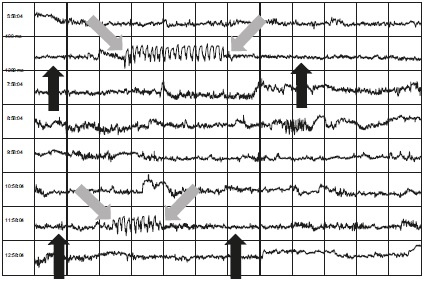

Ниже, на рисунке 7.3, вы увидите анализ ВСР одной из наших студенток, сделанный на продвинутом семинаре. У нее был весьма впечатляющий день. На этом графике отражены две медитации: одна выполнена утром, вторая – перед обедом, и каждый блок представляет пять минут фактической продолжительности. Там, где вы видите первую красную стрелку, указывающую вправо, студентка входит в состояние сердечной когерентности и удерживает его. Во время медитации, проведенной в 6.00 утра, она удерживала это состояние в течение более 50 минут. Там, где вы видите вторую стрелку, указывающую вправо, студентка снова входит в состояние сердечной когерентности на 38 минут во время медитации перед обедом. Вы можете видеть, как она развивает свое умение.

Иллюстрация к книге — Сверхъестественный разум. Как обычные люди делают невозможное с помощью силы подсознания [i_043.jpg]

Рисунок 7.3А

Во время следующей медитации после полудня в тот же день она снова входит в состояние сердечной когерентности, теперь уже на 45 минут. Но самое замечательное происходит вечером, около 20.00 (см. вторую стрелку, указывающую вправо). Поскольку у нас не проводилась общая медитация в это время, мы попросили студентку рассказать о своем опыте.

Она уже собиралась ложиться спать, когда внезапно ее охватило всепоглощающее чувство любви. Оно было настолько сильным, что она должна была лечь и полностью ему отдаться. Ее сердце спонтанно вошло в состояние когерентности, и следующий час и 10 минут, лежа на кровати, она испытывала глубокую любовь к своей жизни. Она произвела автоматические изменения в своей АНС. Там, где вы видите последнюю стрелку, наша студентка, по ее словам, повернулась на бок и уснула. Неплохой способ закончить день, не правда ли?